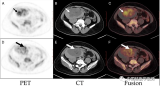

李锋:68Ga-DOTANOC PET/CT发现多灶性肝细胞癌

68Ga-DOTANOC PET/CT显像提示富血管肝脏病变表达生长抑素受体(SR),考虑为该病变为神经内分泌肿瘤,但后来确诊为肝细胞癌(HCC)。由于HCC病变在CT表现为富血管化,可类似神经内分泌肿瘤征象。虽然目前SR-PET/CT成像的适应症中不包含HCC,但在解读神经内分泌肿瘤患者的图像时,可能因HCC造成误诊。SR显像在HCC的诊断价值用仍需要进一步研究证实。 2022-06-05 核医学PET/CT